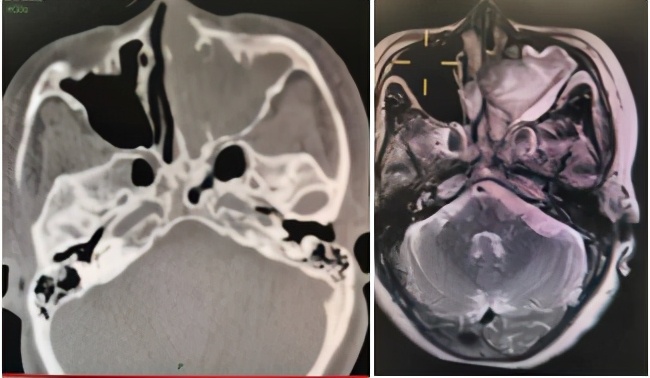

- 同时,医生会询问相关疾病史、用药史、手术外伤史,并配合血清学检查、鼻内镜、鼻窦CT/MR等检查。一方面查找鼻出血原因,从根源上控制鼻出血;另一方面,对于长期或大量出血病人,需评估出血程度,排查贫血、低蛋白血症、失血性休克、其他脏器缺血损伤等情况。

图5. 副鼻窦CT及磁共振(左侧霉菌性上颌窦炎)